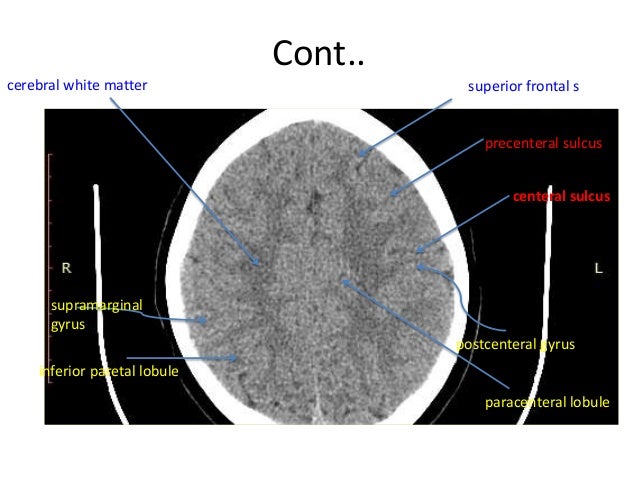

Head Ct

Head ct www.slideshare.net